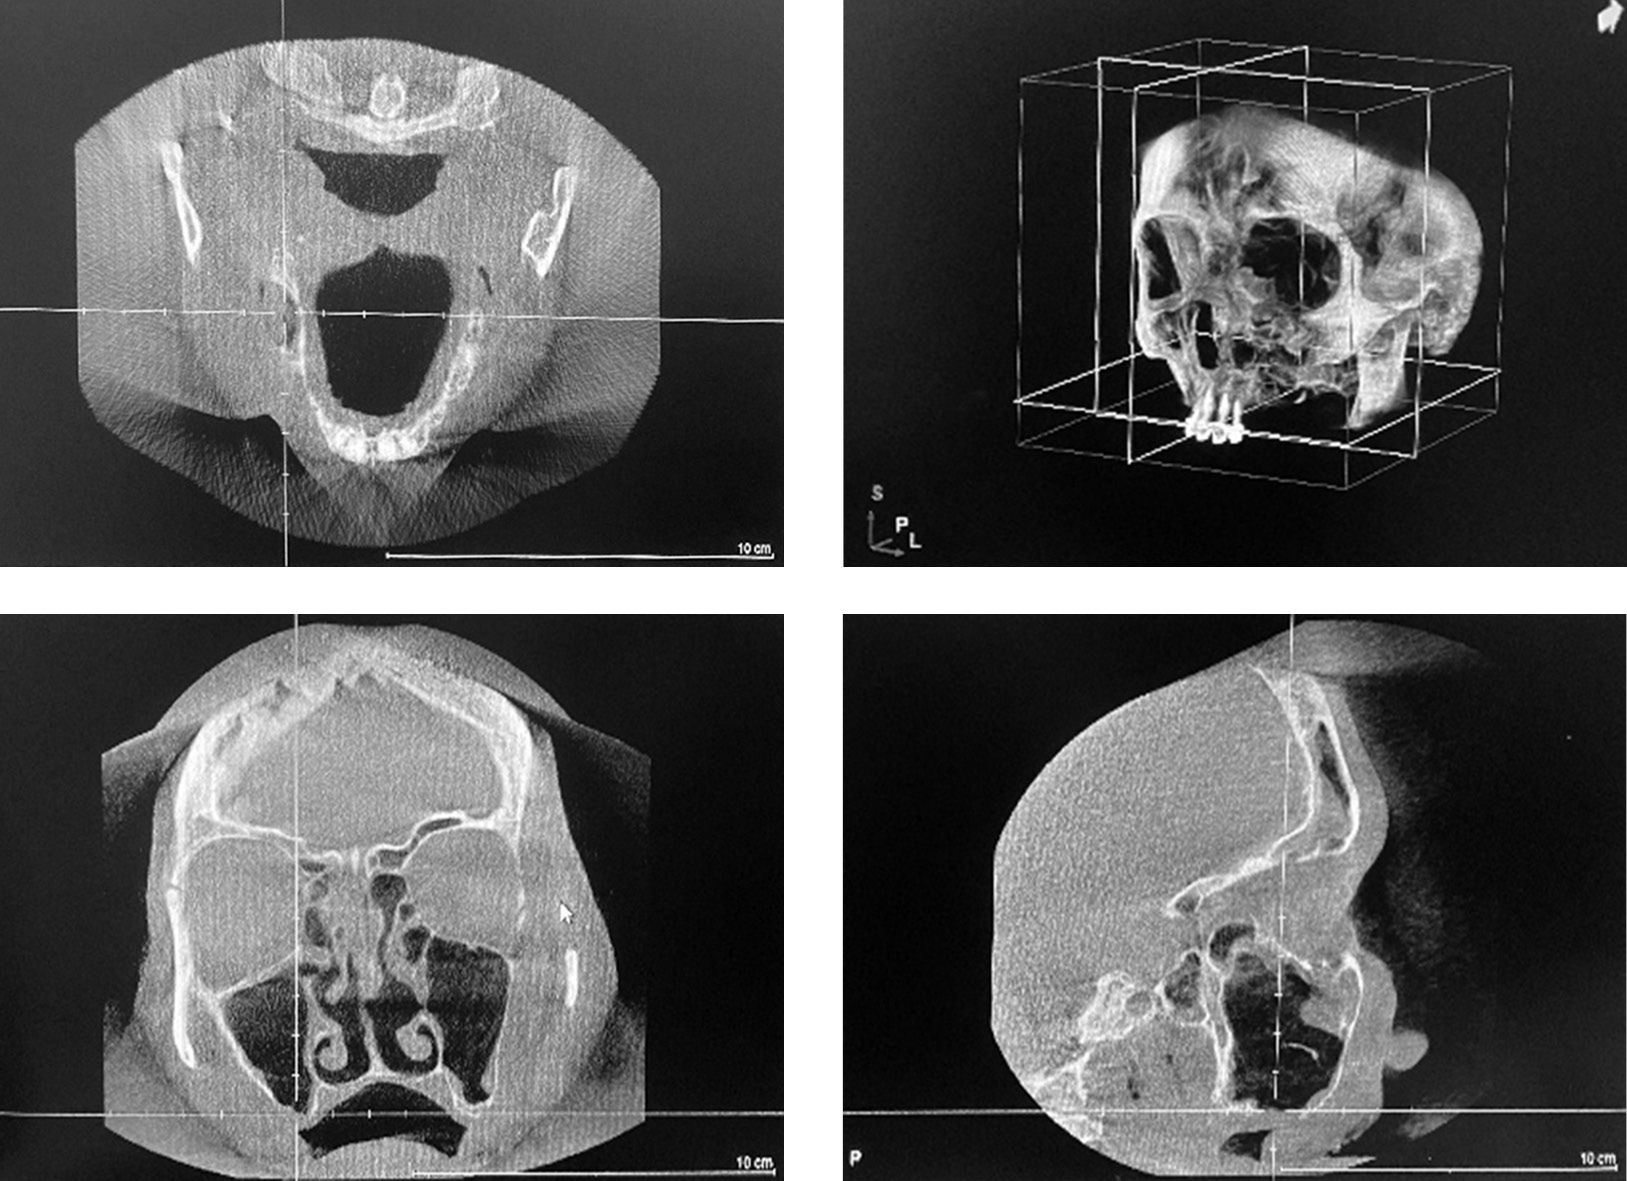

Patient M, 55 years old, was urgently admitted to the Clinic of Otolaryngology of the First Pavlov State Medical University of St. Petersburg with complaints of mucopurulent discharge from the right side of the nose, nasal congestion, more severe on the right side, discomfort in the right side of the face, swelling of the soft tissues of the right cheek area, headache, weakness, and fatigue. The medical history revealed that the patient had 3 episodes of the right maxillary sinusitis in the past 6 months. Sinus radiography followed by conservative and puncture treatment was performed. The effect was positive, but not lasting. Pain in the right side of face and symptoms of intoxication persisted. The most recent episode occurred after hypothermia. Cone beam computed tomography showed a cystic granuloma of tooth 1.6 with shadowing of the right maxillary sinus due to an exudative component (Figure 2). A decision was made to perform an endoscopic right maxillary antrostomy through the middle nasal passage and remove tooth 1.6 concomitantly due to the recurrent sinusitis, soft tissue reaction and the presence of a stomatogenic source of infection. The patient reported pain relief and subjective improvement of the well-being in the postoperative period. The maxillary sinus was irrigated through the widened opening, and the patient received systemic antibacterial, decongestant, and vasoconstrictive therapy. A 3-month follow-up showed complete restoration of sinus pneumatization and healing of the socket of the extracted tooth 1.6. No signs of inflammation were detected.

Fig. 2. Cone beam computed tomography: cystic granuloma of tooth 1.6, shadowing of the right maxillary sinus (an exudative component)

Рис. 2. Конусно-лучевая компьютерная томография: кистогранулема зуба 1.6, затенение правой верхнечелюстной пазухи (экссудативный компонент)